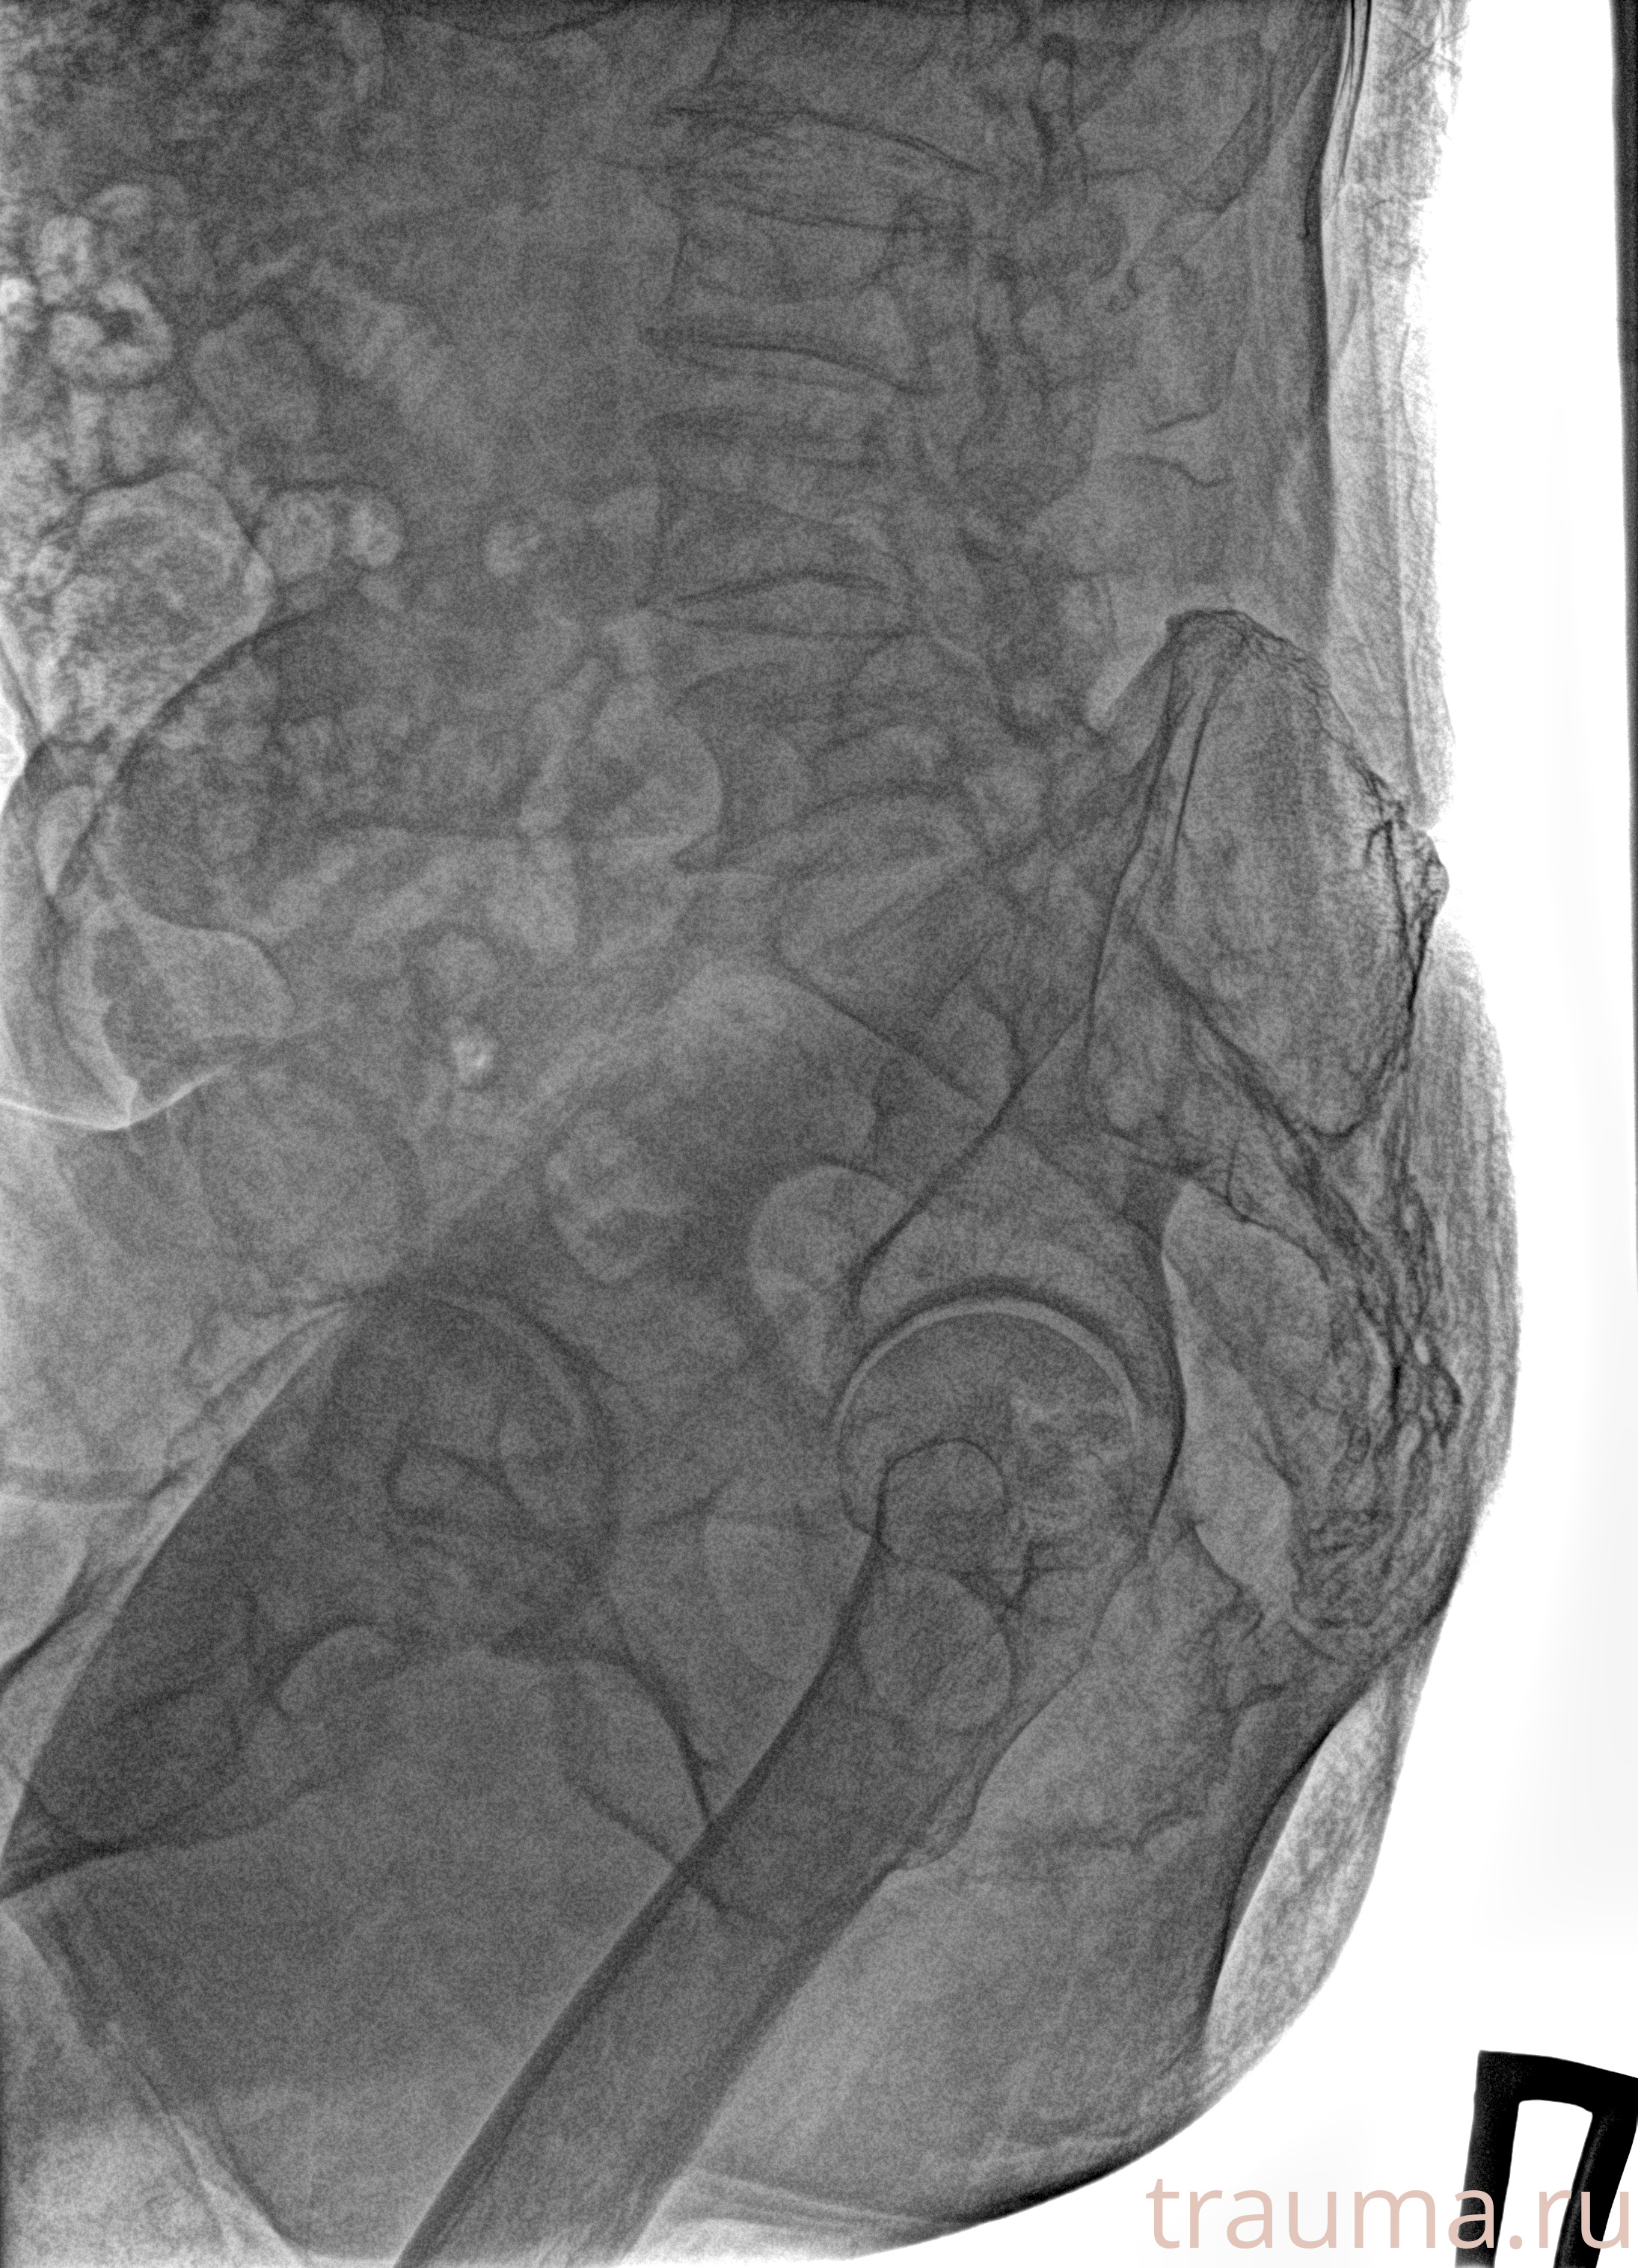

Рентгенограммы

Рентген на дому: по вашему адресу приезжает врач-рентгенолог, травматолог-ортопед с мобильным рентгеновским аппаратом, проводит диагностику травмы или заболевания, делает необходимые рентгенограммы, дает рекомендации по дальнейшему лечению. Получить качественные снимки в домашних условиях возможно благодаря уникальной методике, разработанной МосРентген Центром для института  Склифосовского